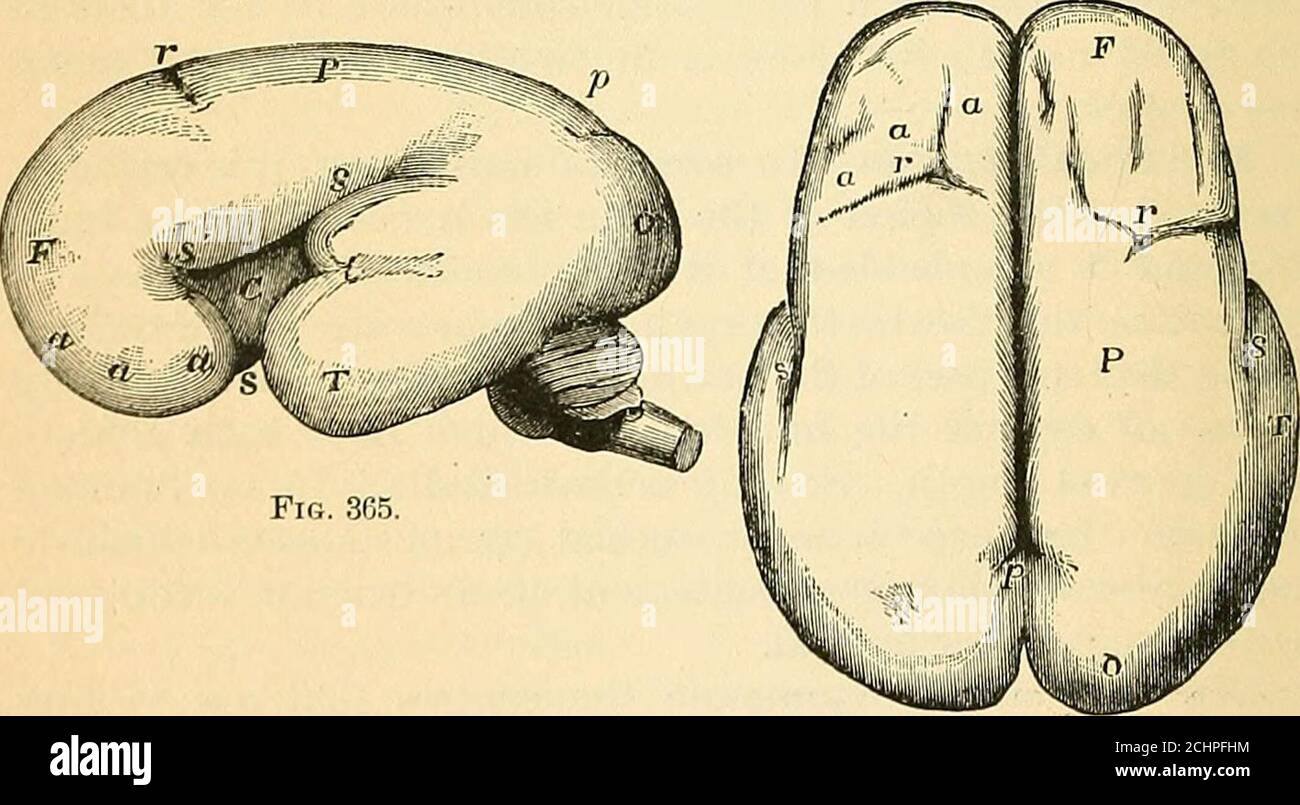

RM2CHPFHM–. Ein Lehrbuch der vergleichenden Physiologie für Studenten und Praktiker der vergleichenden (Veterinär-)Medizin . Abb. 364. – Vertikaler Längsschnitt des Gehirns des menschlichen Embryos von vierzehn Wochen.1x3. (Nach Sharpey und Reichert.) c, zerebrale Hemisphäre; cc, corpus callosumbeginning to Pass back; /, Foramen von Munro; p, Membran über dritten Ventrikel und der Zirbelkörper; th, Thalamus; 3, dritten Ventrikel; /. Olfaktorische Glühbirne; cq, corporaquadrigemina; cr, crura cerebri, und über ihnen, Aquädukt von Sylvius, noch breit;c, Kleinhirn, und unter ihm die vierte Ventrikel; jw, pons Varolii; m, medullaoblongat

RM2ANFGX0–Quain der Elemente der Anatomie. ring Abb. 729.-op ein Bild. 729. Längsschnitt durch das Gehirn OFA KÜKEN VON ZEHN DATS. (Nach Mihalkovics.) h, zerebralen Hemisphäre; olf, oKactory lobe und Nerv; St, Corpus striatum; iv, lateralventricle; ac, anterior com-missure; Er, der Lamina terminalis; ope, Optic commissure; Grube, der Hypophyse; inf inf Undi-bulum; Cai, interne carotidartery; v^, dritten Ventrikel; ch?, Choroid plexus dritter Ventrikel; Pin, zirbeldrüse; Ijg, Korpora bigemina; amv, anterior medullary Velum; unten - n - hich zwei letzte Referenzen sind das Aquädukt von Sylvius und crur

RM2CH08HM–. Quains Elemente der Anatomie . Enient zu bringen Feige. 729. – UMRISS EINES LÄNGSSCHNITTS DURCH DAS GEHIRN OFA-KÜKEN VON ZEHN DATS. (Nach Mihalkovics.) h, zerebrale Hemisphäre ; Olf, olfaktorische Lappen und Nerven ; st,corpus striatum ; IV, lateralventricle; ac, anterior com-misure; Es, lamina terminalis;op, optic commissure ; Piit,pituitäre Drüse ; inf, infundi-bulum ; cai, interne cardartery ; ?••*, dritte Oticle ; Plexus ; Plexus ; Plexus ; Plexus hg, corpora bigemina ; amt anterior medullarj velum ;unter welchen zwei letzte Referenzen das Aquädukt von Sylvius und sind